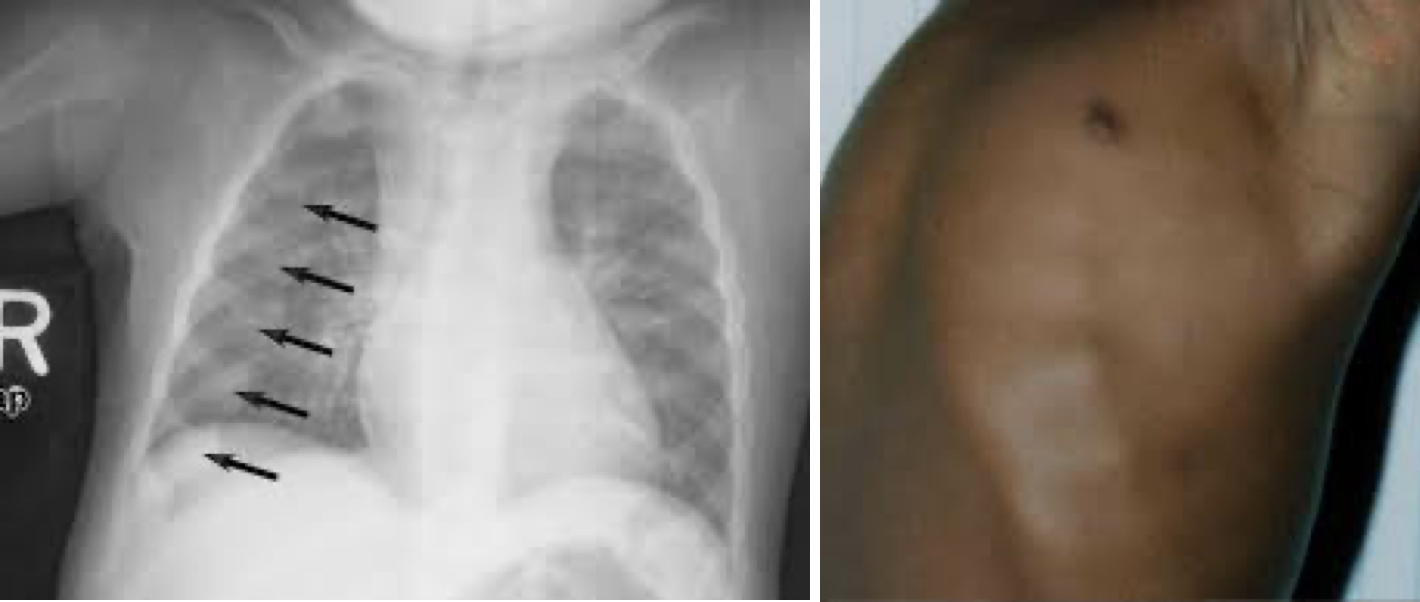

• 비타민 C (Ascorbic acid): 콜라겐 합성, 항산화, 철분 흡수 촉진. 결핍 시 괴혈병(Scurvy)